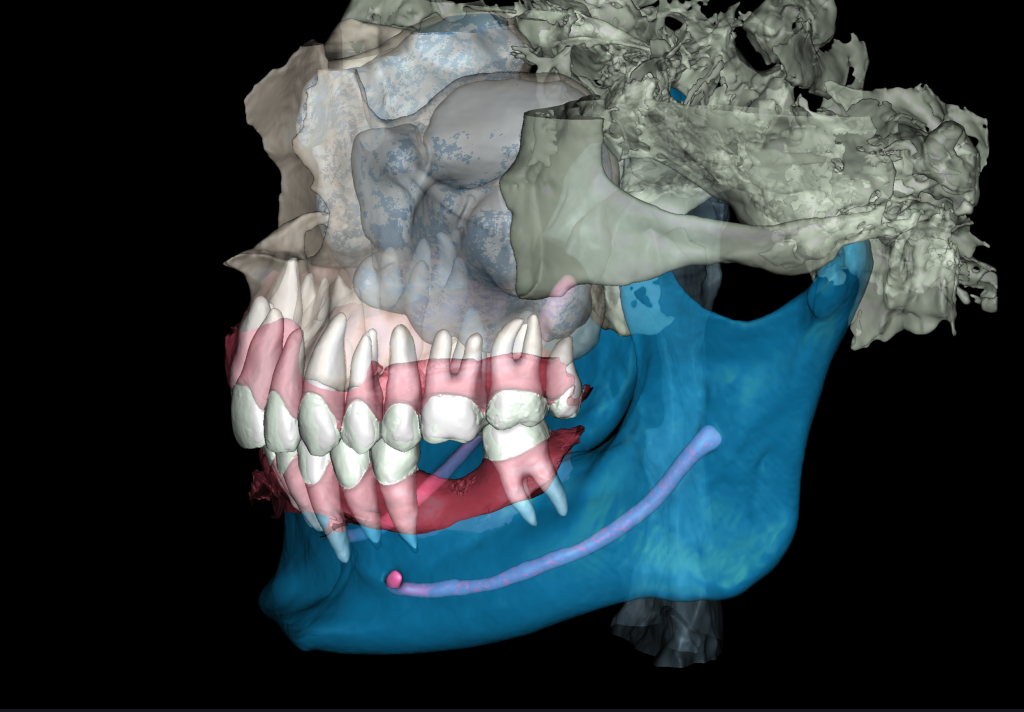

Врач может загрузить данные внутриротового сканирования в STL модуль и получить 3D-модель для выбора оптимального положения имплантата и планирования навигационного шаблона